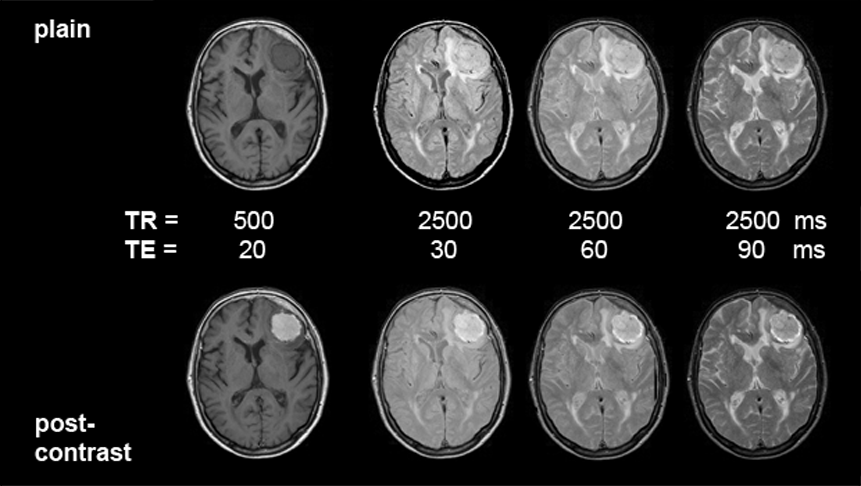

spaceholder darkblueImaging parameters. Because paramagnetic contrast agents are T1-agents, their effect is most pronounced on T1-weighted MR images, for instance on spin-echo images with short repetition and echo times, and gradient-echo ima­ges with short repetition times and high flip angle (50°-90°). Intermediately (ρ) weighted images will still show enhancement. The agents lose most of their efficiency on T2-weighted pictures; in many cases, even an isointense behavior can be observed (Figure 13-09).

Figures 13-09:

Pa­tient with a meningioma. Multiple SE sequence before (top row) and after (bottom row) intravenous application of a gadolinium contrast agent. The images to the left are heavily T1-weighted, then ρ-weighted, and to the right increasingly T2-weighted.

Simulation software: MR Image Expert®

Animation of contrast-enhanced images; pa­tient with a meningioma; TR = 800 ms; TE bet­ween 20 and 120 ms (= T1-weighted to T2- in­flu­en­ced). The contrast-agent enhancement of the tumor slowly disappears (cf. Figure 13-08 a; plain images and enhanced images).

The patient of the figure above has a huge meningioma in the left frontal lobe. It is easily visible on the non-enhanced images, mostly because of its mass effect and the bright surrounding edema on T2-weighted images. Yet, this case is a good example of the enhancement pattern of gadolinium contrast agents. This kind of tumor enhances brightly on T1-weighted images; there is still enhancement on ρ-weighted images. T2-weighted images, however, show the same contrast pattern before and after injection of the agent. If the meningioma or similar enhancing lesions are very small and no indirect signs of lesions can be found, only contrast enhancement will reveal the pathology (see also Figure 13-04 and Figure 13-08).